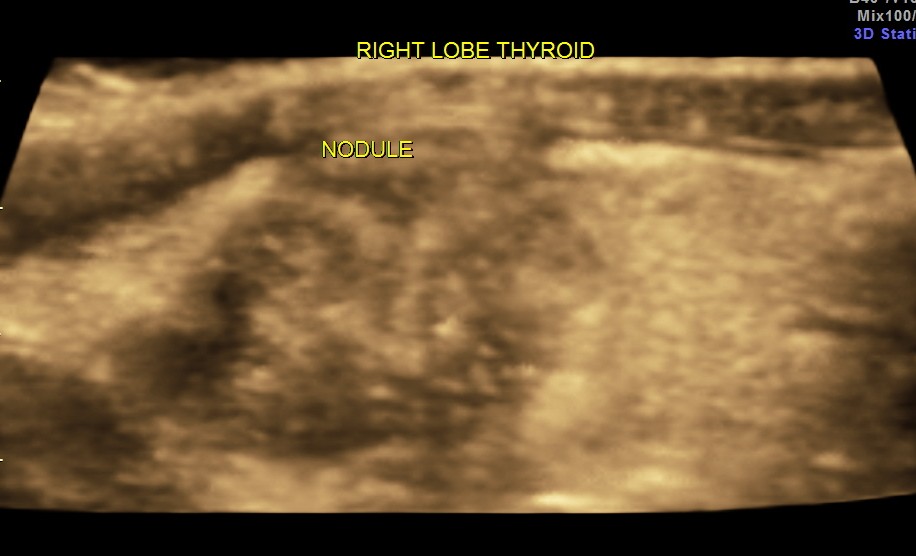

The right lobe of the thyroid revealed an irregular mass , with indistinct margins , punctate calcification and vascularity within and around the nodule.

The 3 D glass body reconstruction clearly shows vascularity within and surrounding the mass.

The 3 D reconstruction images very clearly show the indistinct and irregular margins and the punctate calcification.